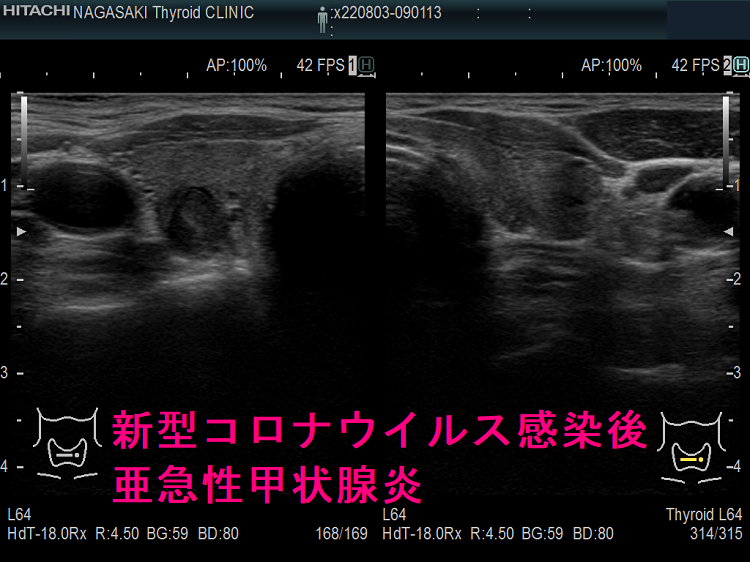

以下は、長崎甲状腺クリニック(大阪)の自験例です。

長崎甲状腺クリニック(大阪)の自験例

急性期

1.5か月後

5か月後